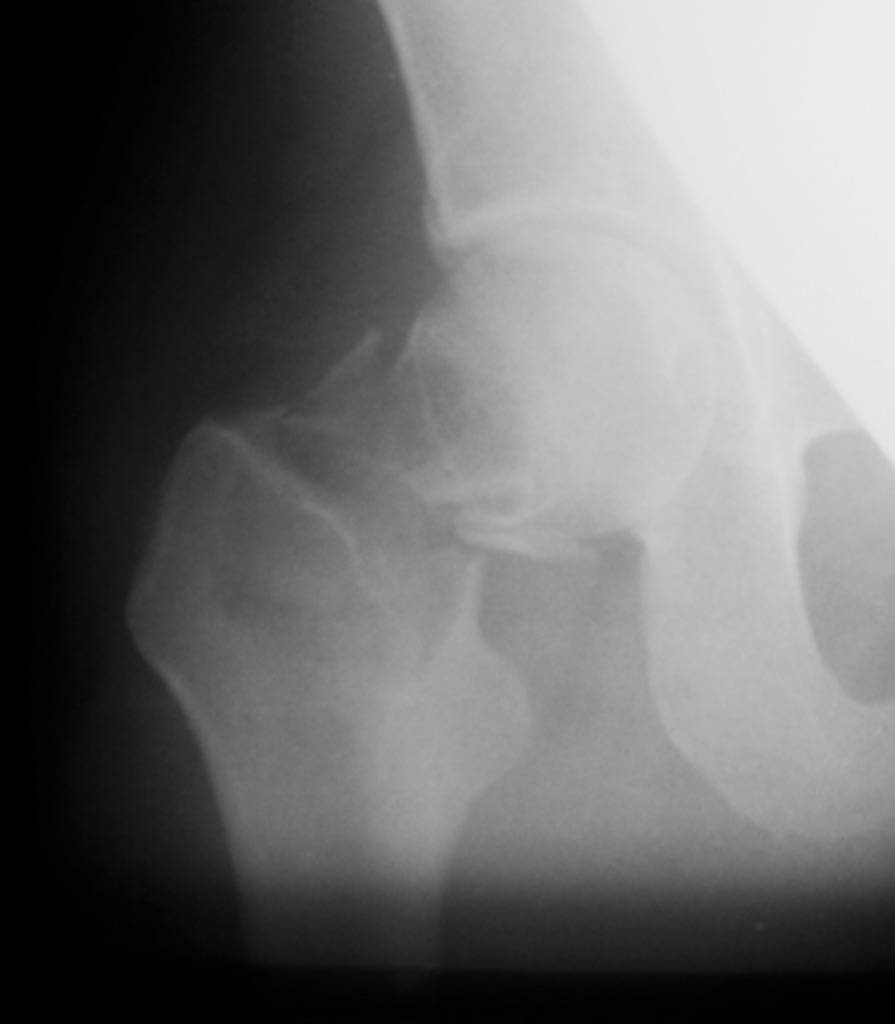

[Ortho] Патологический перелом шейки + беременность

"Поправил" рентгенограмму. Так не лучше?